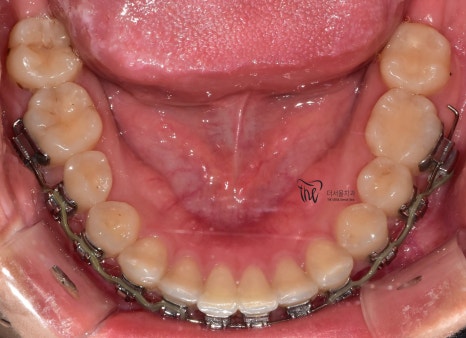

따라야 되는데 교합면 사진을 보게 되면

뭔가 전체 치열 자체는 고르게 느껴지죠?

근데, 이거 다 끝난게 아닙니다.

아직, 치아 얼라이먼트가 완성이 되지 않았습니다.

치아 얼라이먼트라는 것은 치열이 U 자 형태로

둥글게 악궁을 형성하고 있어야 되는데 살짝살짝

군데군데 아쉬운 점이 남아있습니다.

그러면서, 치아 레벨링이 완성이 되질 않았습니다.

레벨링 이라는 것은 위, 아래 치아들을 동시에

놓고 봤을 때의 가지런함을 뜻합니다.